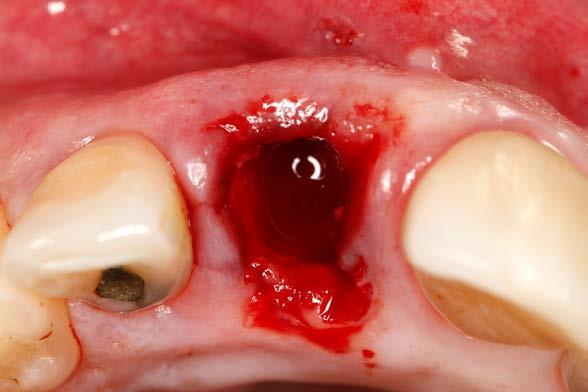

Una vez colocado el implante y el transepitelial para elaborar la prótesis de carga inmediata se realiza el sellado del gap vestibular, en este caso empleando únicamente PRGF-Endoret. El procedimiento es igual que

9 y 10. Relleno del gap con PRGFEndoret, situando un coágulo recién activado de la fracción 2 en el fondo del alveolo y posteriormente un tapón de fibrina para la zona más superior (fracción 1 activada y retraída).

para el sellado de un alveolo postextracción, colocándose un coágulo de PRGF-Endoret recién activado de la fracción 2 (con alta liberación de factores de crecimiento) y sobre el mismo un tapón de fibrina autóloga sellando la zona más cercana al reborde alveolar (Figura 9 y 10). No se utilizan puntos de sutura para evitar el colapso del tejido blando del alveolo, además que por la adhesividad de la fibrina se mantiene en

posición sin necesidad de suturarla. A los 3 días podemos colocar la corona confeccionada de carga inmediata y vemos en la imagen antes de hacerlo la correcta epitelización de los tejidos blandos alrededor de la tapa de protección del transepitelial (Figura 11).